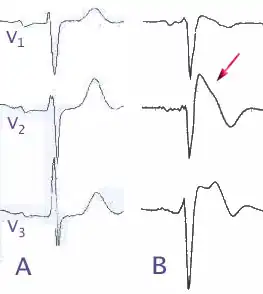

Bien que le tracé caractéristique du syndrome de Brugada pourrait être vu sur un électrocardiogramme au repos, on observe souvent le tracé anormal soit après l'administration de drogues comme l'ajmaline ou la flécaïnide, soit en la présence de triggers encore indéterminés. L'ajmaline est utilisée par voie intraveineuse pour diagnostiquer le syndrome de Brugada, puisqu'ils affectent tous les deux les canaux sodiques[12] : l'administration d'ajmaline à une personne souffrant d'un syndrome de Brugada provoque l'apparition d'un tracé caractéristique sur l'ECG, ou le segment ST est anormalement élevé au-dessus de la ligne de base. En raison des complications qui pourraient survenir pendant le test à l'ajmaline, l'injection par un infirmier spécialisé et la présence à proximité d'un défibrillateur sont des éléments indispensables.